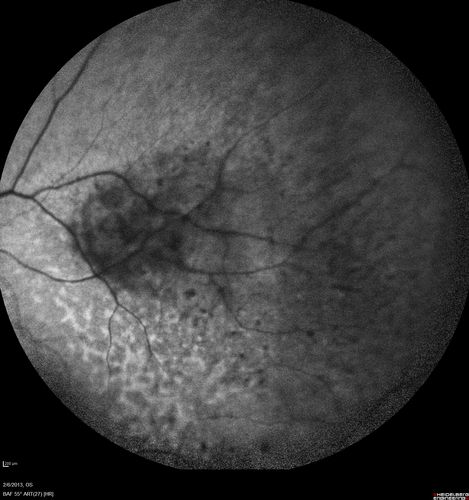

Vasculitis - Retinitis - Uveitis - Vision NLP right eye , 20/50 left eye

Unknown - Possible Syphilitic